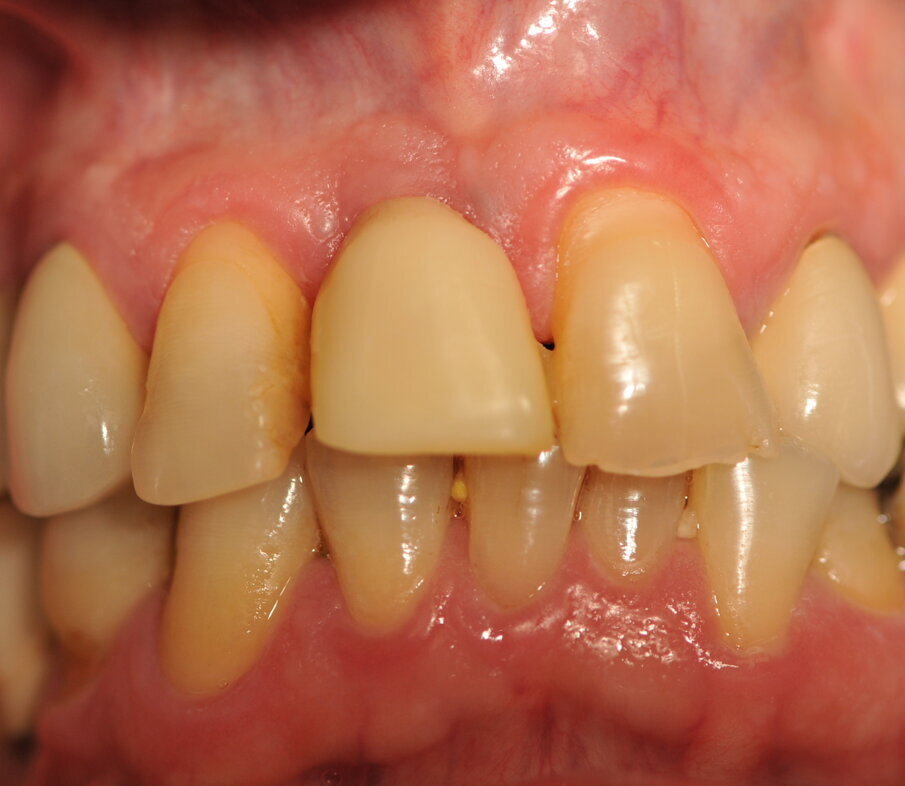

Fig. 11_Corona definitiva a 1 mese dalla cementazione.

Paziente di sesso maschile di 60 anni di età giunto alla nostra osservazione per una edentulia parziale dovuta all’assenza dell’elemento 1,1. La situazione clinica è resa esteticamente e funzionalmente complicata dalla assenza dell’elemento 2,2 che considerato lo spostamento dei denti contigui comporta un aumentato spazio per la sostituzione protesica dell’elemento 1.1. Si effettua dopo rx di controllo il posizionamento di un impianto osteintegrato GTB diametro 3,6 x 9 mm ,con posizionamento, come da protocollo, 1,5 mm sottocrestale ed inserzione immediata di moncone easy abutment slim 3,4 x 7 mm altezza gengivale 3,5 mm. angolato a 10 gradi (Easy Abutment Slim – GTB Plan1Health Amaro, UD, Italy). Con l’ausilio di una cappetta easy si costruisce e si cementa, con tecnica extraorale, una corona provvisoria in resina acrilica con forma a pontic su elemento 1.1 in modo da eseguire un carico immediato e fornire al paziente una estetica immediata (Figg. 1-3). Dopo 12 settimane ad avvenuta osteointegrazione si provvede all’impronta definitiva eseguita a livello abutment con elastomero di precisione Aquasyl Monophase (Dentsply) e con idonea cappetta easy (GTB Plan1Health Amaro, UD, Italy). La stessa cappetta easy viene utilizzata dal laboratorio odontotecnico come cappetta da sovrafusione garantendo standard di precisione stabiliti industrialmente (Figg. 4-8). La corona costruita in lega preziosa e porcellana viene cementata dopo una settimana, fatte le prove estetiche e occlusali necessarie sul paziente. I controlli a distanza di 4 anni, sia radiografici che clinici, confermano la stabilità dell’osso intorno all’impianto e la mancanza di perdita di tessuto gengivale attorno allo stesso (Figg. 9-11).